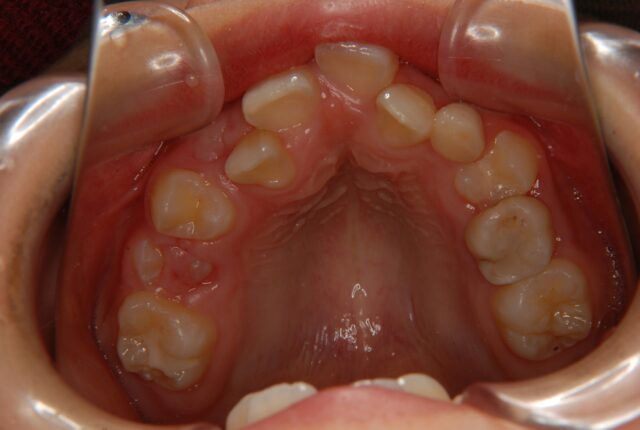

唇側矯正 小児矯正 反対咬合(受け口)の治療例【非抜歯】 この治療例は上下顎歯の唇側より矯正装置を装着して、反対咬合の改善を行った写真です。 治療前 治療後 主訴 受け口を治したい 診断名あるいは主な症状 下顎前突 年齢 10才 治療に用いた主な装置 唇側矯正装置 抜歯部位 非抜歯 治療期間 約2年 通院回数 24回 治療費概算 880,000円(税込) リスクと副作用 反対咬合を改善する時に上下の歯がぶつかり破折する可能性がある。下顎が後方に押し込まれ、顎関節に負担をかける可能性がある。